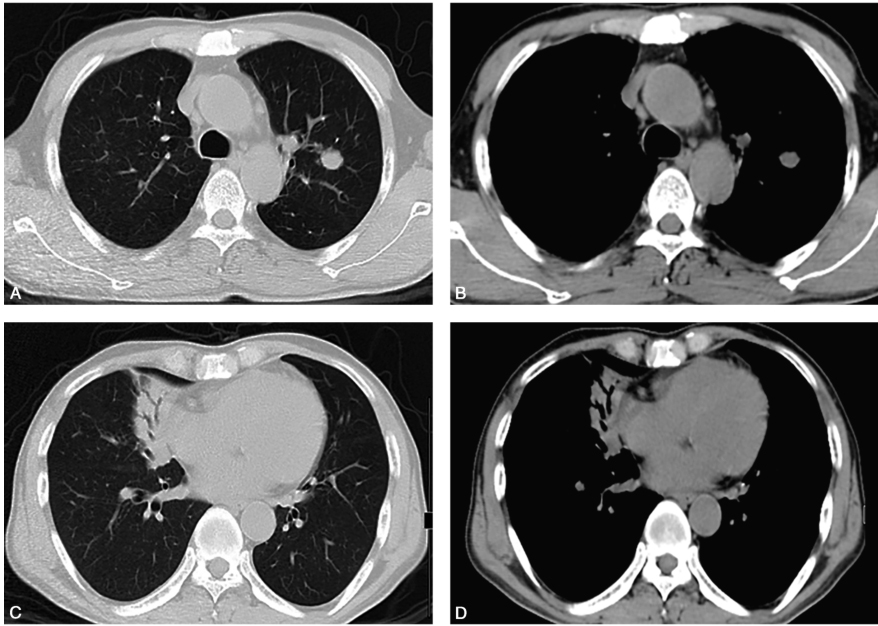

胸部CT(2013-12-18,图1):右肺中叶大片高密度影,伴支气管充气征;双肺多发结节影;纵隔淋巴结肿大。

图1 胸部CT:右肺中叶大片高密度影,伴支气管充气征;双肺多发结节影;纵隔淋巴结肿大